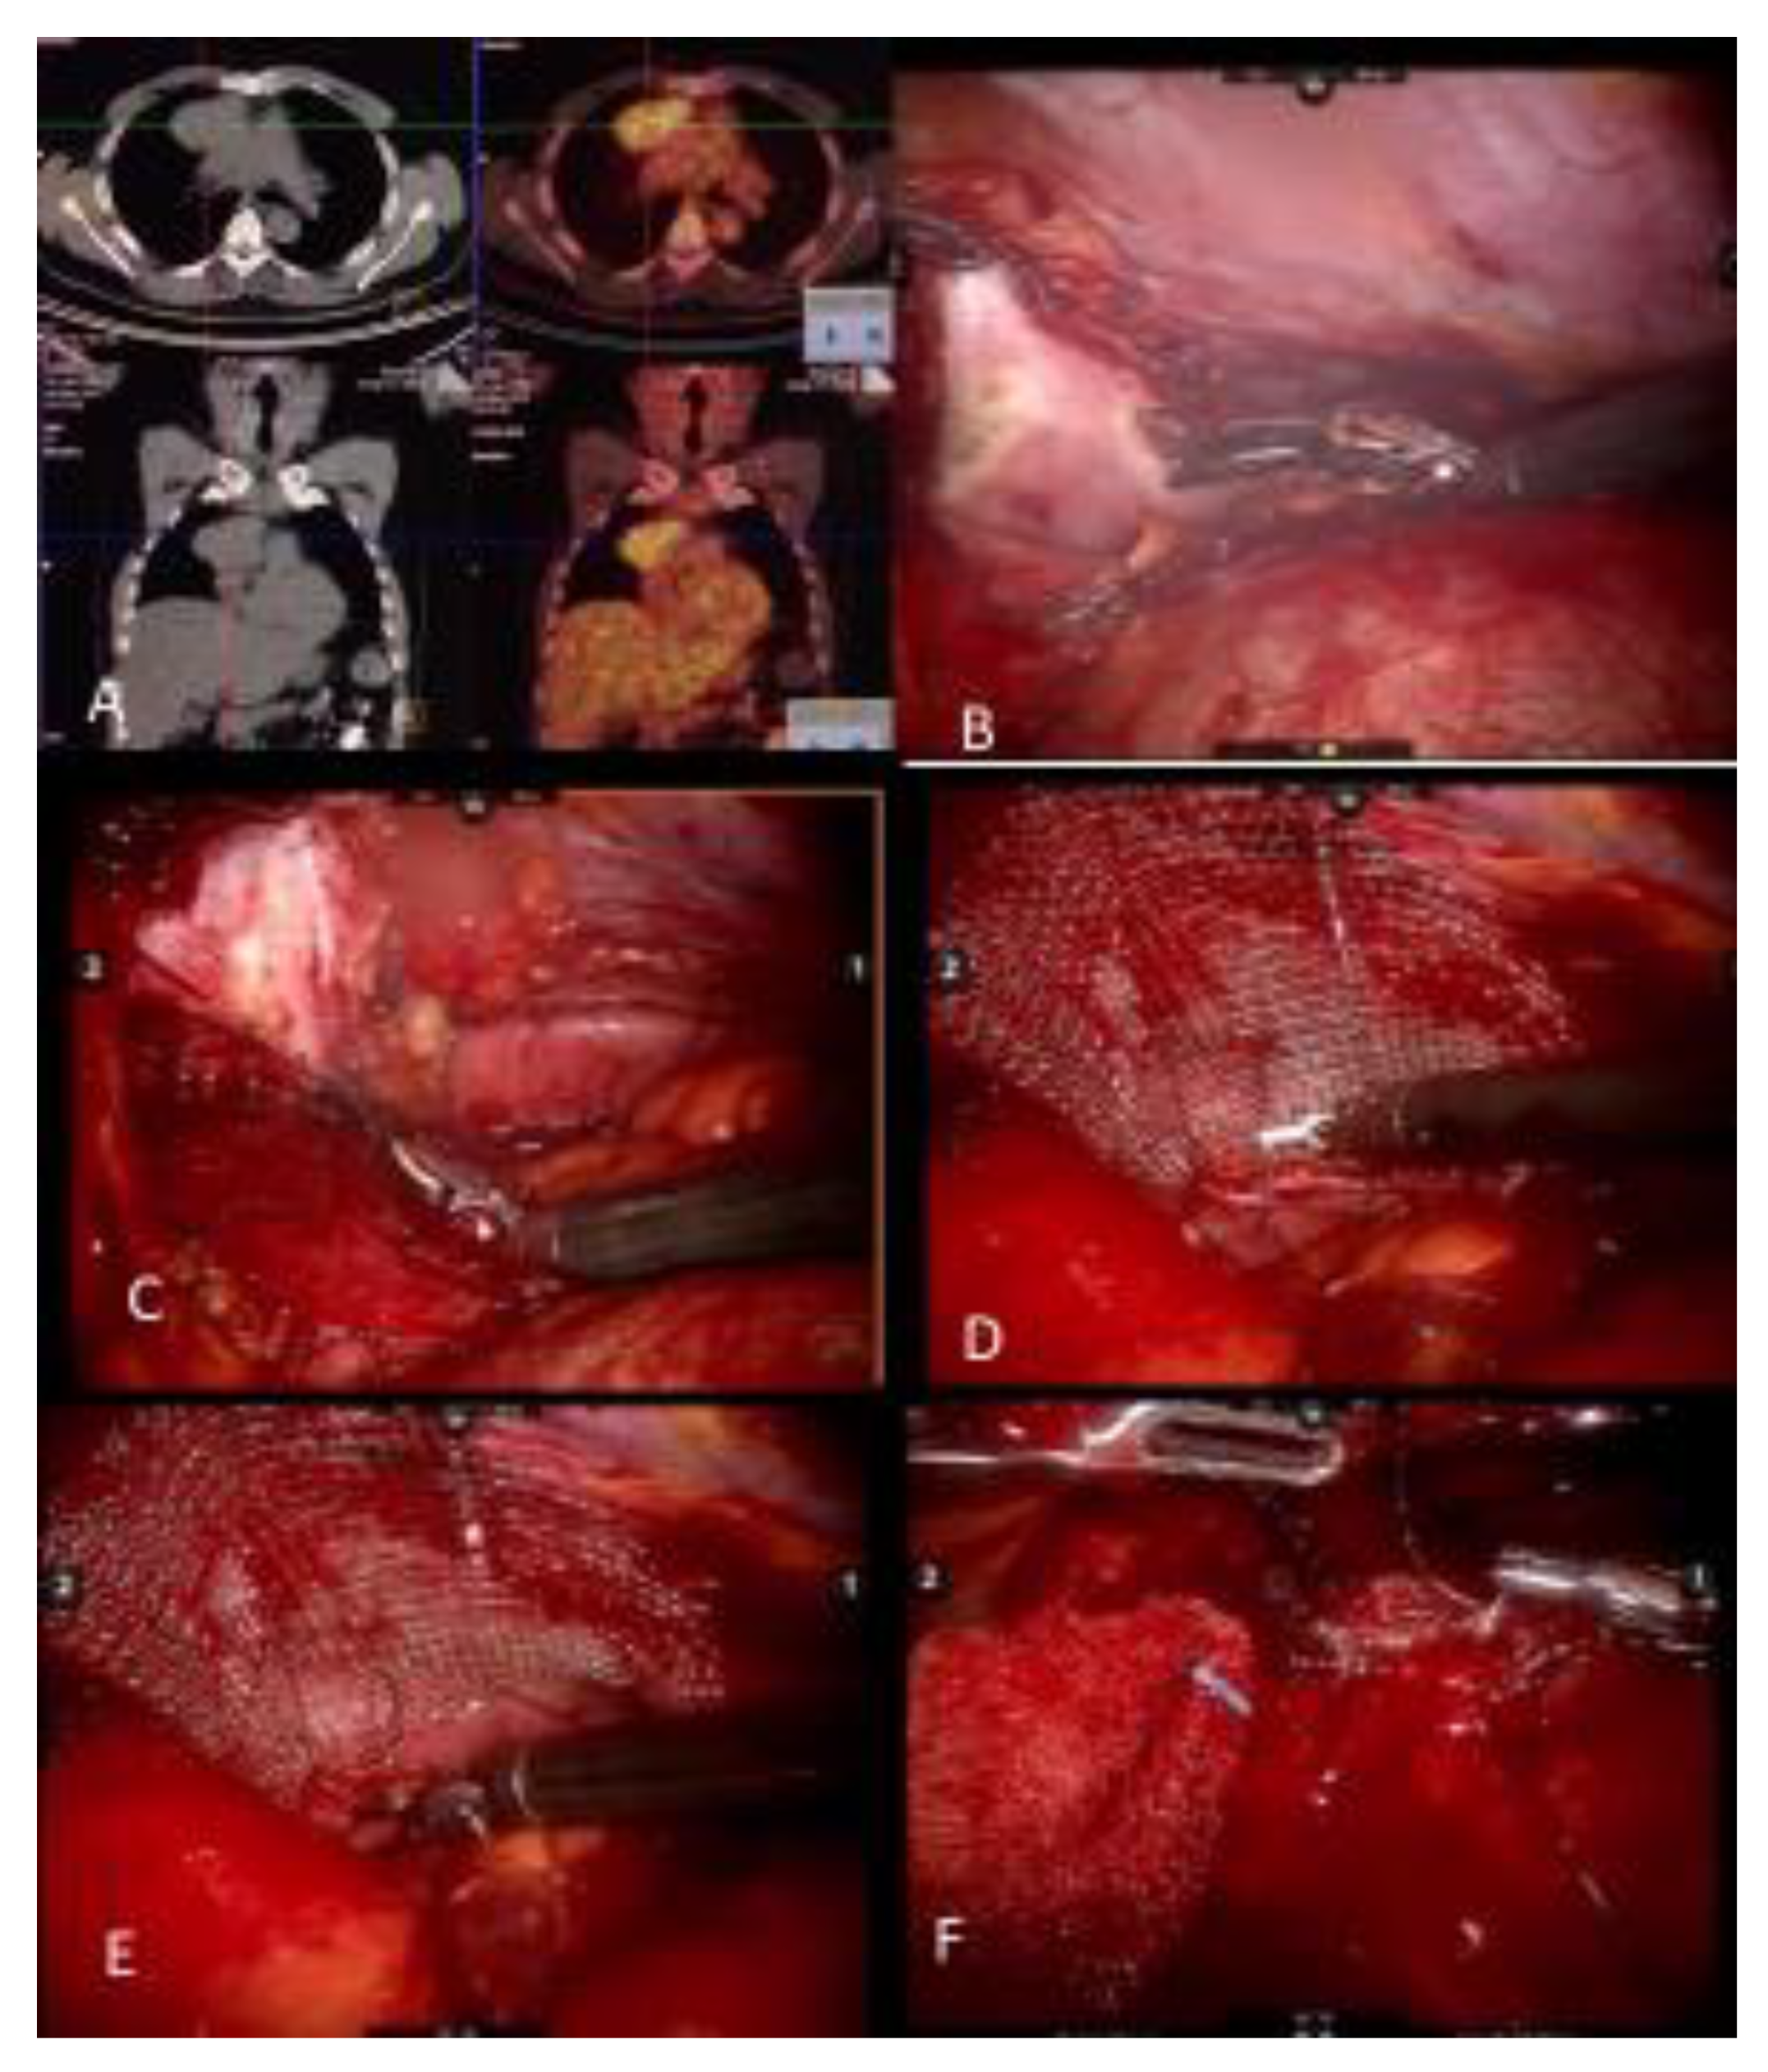

Figure 1.

(A) Noncontrast CT of a myasthenia gravis patient with a thymoma and PET CT demonstrating FDG uptake. (B) Pericardial resection using the robotic bipolar instrument. (C) Invasion of pericardium may be deep in the left chest and may require upward traction up the pericardium. It is important to identify and preserve the left phrenic nerve from medial and internal side of the pericardium. (D) When reconstructing the pericardium with a graft, the first suture placed allows upward traction of the hilar pericardium. (E) A continuous suture technique with barbed sutures is preferred when reconstructing the pericardium. (F) As the left hilar pericardium is pulled up, attention should be given to not place the graft too tight as to constrict the heart.